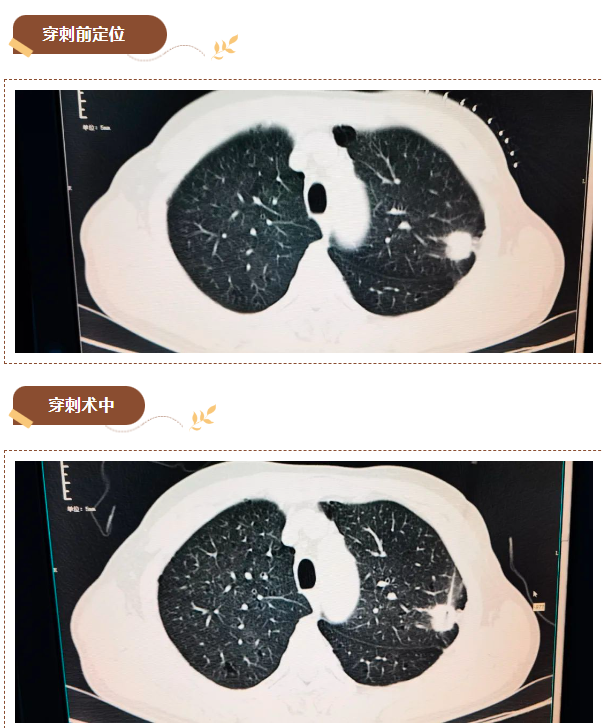

经会诊,决定以最小的微创检查方式明确诊断肿瘤性质,为患者实施“CT引导下行经皮肺穿刺活检术”。

遂完善胡先生的术前检查,并对可能出现的并发症做了充分评估后,放射科医生在螺旋CT机精确引导下进行CT引导下穿刺活检,成功取得病检标本,整个手术过程顺利,用时仅20分钟,术中和术后患者无明显不适,病理结果提示(左肺上叶穿刺组织)腺癌。